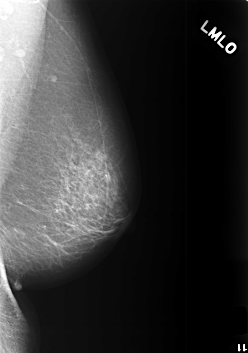

C_0412_1.LEFT_MLO

C_0412_1.LEFT_CC

LEFT_MLO LINES 5640 PIXELS_PER_LINE 3960 BITS_PER_PIXEL 12 RESOLUTION 50 NON_OVERLAY